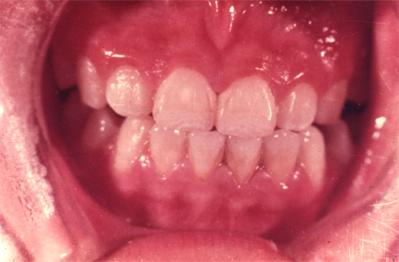

儿童牙齿发育过程中摄入过量的氟会引起氟斑牙:

可疑:上中切齿唇面有白色薄雾状或条状白色横纹

极轻度:上中切齿唇面有条状白色斑纹,占牙面1/4以下。

轻度:白色条纹或斑块,占牙面1/2以下,可出现浅棕色着色。

中度:上中切齿或全口牙整个牙面出现白垩,失去光泽,有明显着色。有的出现小点状凹坑。

重度:全口牙面呈白垩,出现散在坑凹状缺损或融合成片状缺损,有较重的着色。